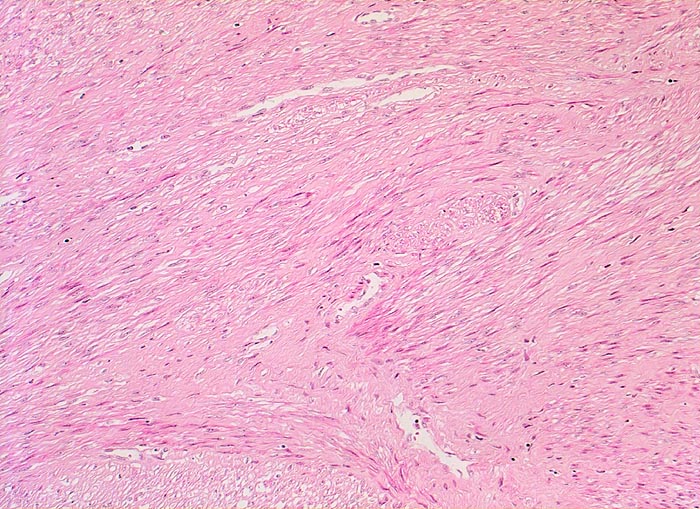

PathoPic – image database / PathoPic ID 4438 - Fibroleiomyom

Fibroleiomyom

benigner Tumor

Uterus

Die glattmuskulären Tumorzellen bilden geflechtartig verwobene, teils orthogonal, teils längs verlaufende Bündel. Zwischen den Tumorzellen verlaufen unterschiedlich breite zellarme Kollagenfaserzüge.

Vergrösserter 258g schwerer Uterus mit multiplen weissen, derben scharf begrenzten, teils intramuralen und teils submukös gelegenen Knoten.

Vaginale Hysterektomie wegen Meno-Metrorrhagien.

100